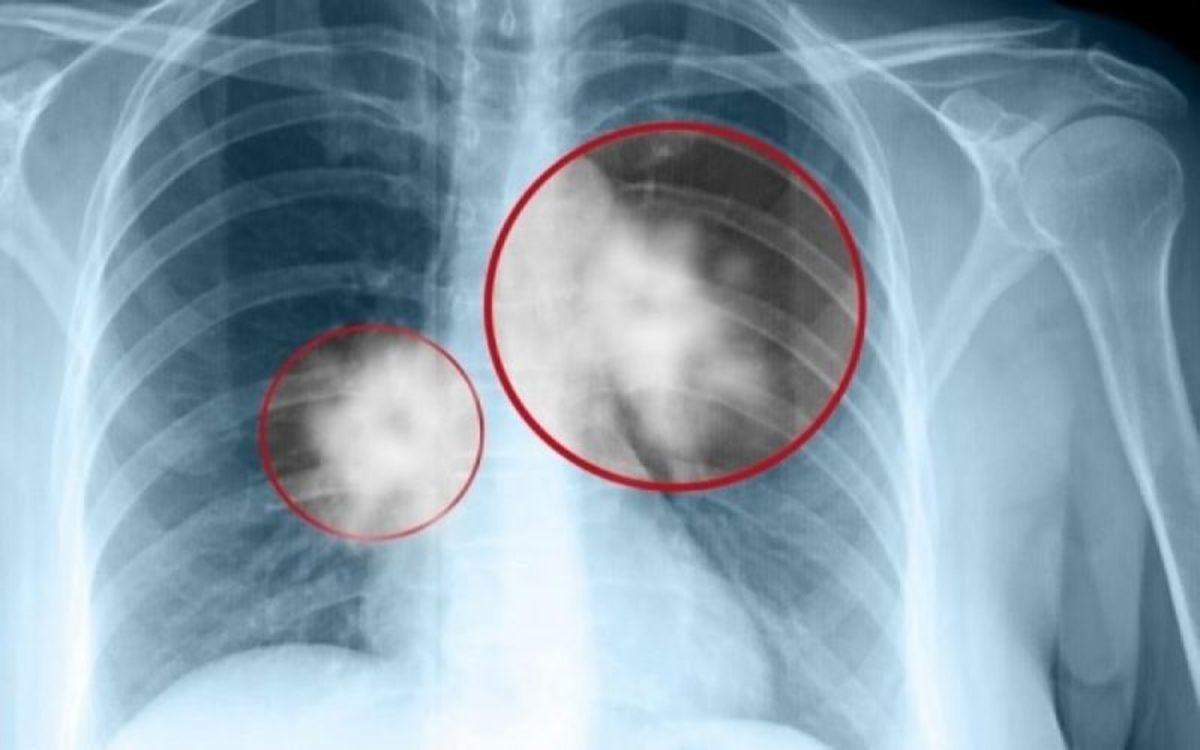

Καρκίνος πνεύμονα: Νέα θεραπεία δίνει ελπίδες

Ο Αμερικανικός Οργανισμός Τροφίμων και Φαρμάκων (Food & Drug Administration), βασιζόμενος και στα πρόσφατα αποτελέσματα μελετών που παρουσιάστηκαν στο Ευρωπαϊκό Συνέδριο Κλινικής Ογκολογίας ESMO τον περασμένο Σεπτέμβριο, ενέκρινε το pembrolizumab ως αρχική θεραπεία (θεραπεία πρώτης γραμμής) για ασθενείς με μεταστατικό μη μικροκυτταρικό καρκίνο του πνεύμονα.